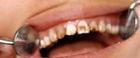

1.牙面颜色有改变,呈棕色。

2.牙可有带状、窝状凹陷。

3.牙面可见平行横线。

4.切缘变薄。

6.对称性发生。

7.多发性缺损。